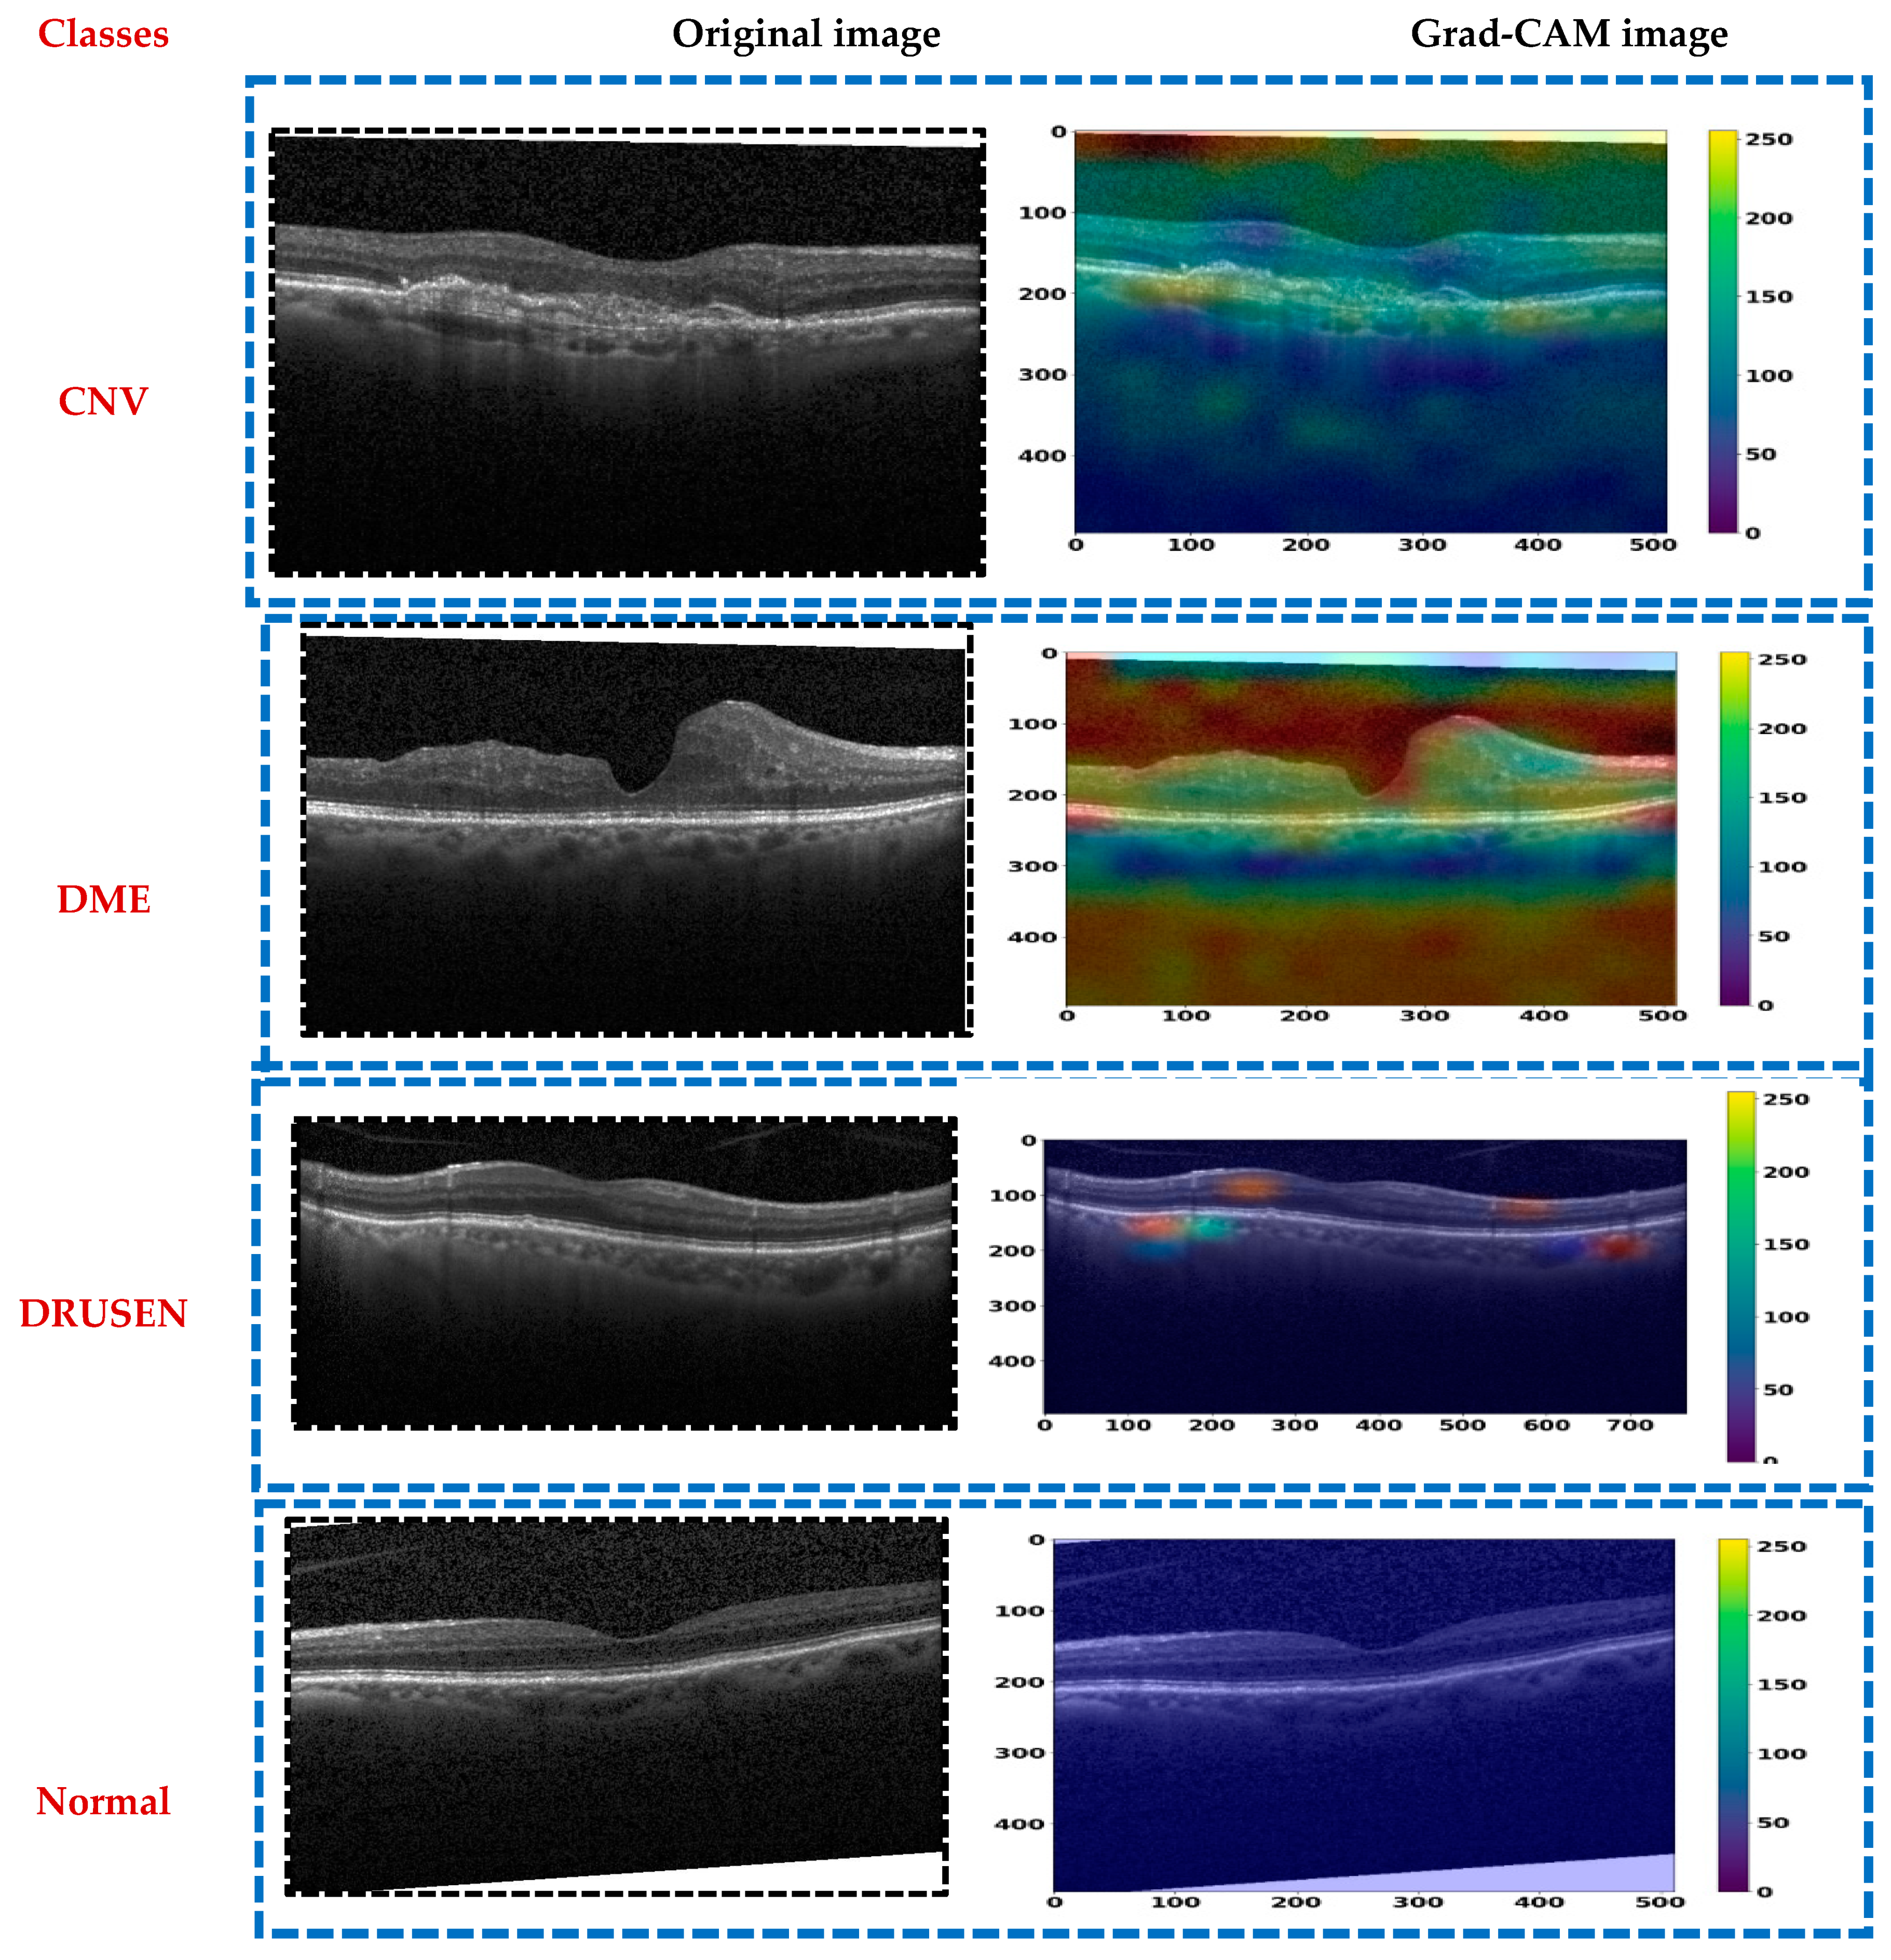

- We performed a comprehensive experiment utilizing two OCT datasets, incorporating Grad-CAM to analyze the model’s decisions and offering visual explanations.

- The authors of the earlier study did not utilize the Grad-CAM algorithm. On the other hand, we implemented this algorithm to identify specific areas impacted by ground glass opacities (GGOs) that correlate with EDs.

In this section, we describe the evaluation metrics utilized to assess the proposed model. We will cover the overall classification performance, conduct statistical analysis, present ablation studies and visual explanations via Grad-CAM, and compare our findings with previous work.

In summary, CDResNet101-V2 emerged as the most reliable model based on its narrow and high confidence interval range, while EfficientNet-B3 displayed the most variability and lower bounds, suggesting room for improvement in its performance.

From Table 10, CDResNet101-V2 exhibited an impressive confidence interval ranging from 98.78% to 99.77%. It maintained high reliability with one of the narrowest and highest intervals, indicating consistent performance. MobileNet-V2 achieved a confidence interval range of 98.15% to 99.67%. While it demonstrated strong upper bound performance, its lower bound was slightly lower compared to other leading models, reflecting a bit more variability. EfficientNet-B0 showed a confidence interval range of 98.35% to 99.71%. It demonstrated robust performance with a relatively narrow range, indicating consistency. EfficientNet-B3 exhibited a confidence interval range of 98.60% to 99.74%. Its range was slightly narrower and higher than that of EfficientNet-B0, indicating marginally better reliability. NASNetMobile presented the widest confidence interval range, from 97.34% to 98.92%. This indicated a lower and more variable performance compared to other models, suggesting a need for improvement. ResNet50 achieved a confidence interval range of 98.65% to 99.77%. It matched the upper bound of CDResNet101-V2 and demonstrated strong reliability with a high and narrow range.

In summary, CDResNet101-V2 and ResNet50 distinguished themselves with exceptional upper bounds and narrow intervals, signifying highly consistent and reliable performance. Conversely, NASNetMobile exhibited the lowest and most variable range, highlighting its comparatively weaker consistency.

4.4. Ablation Study